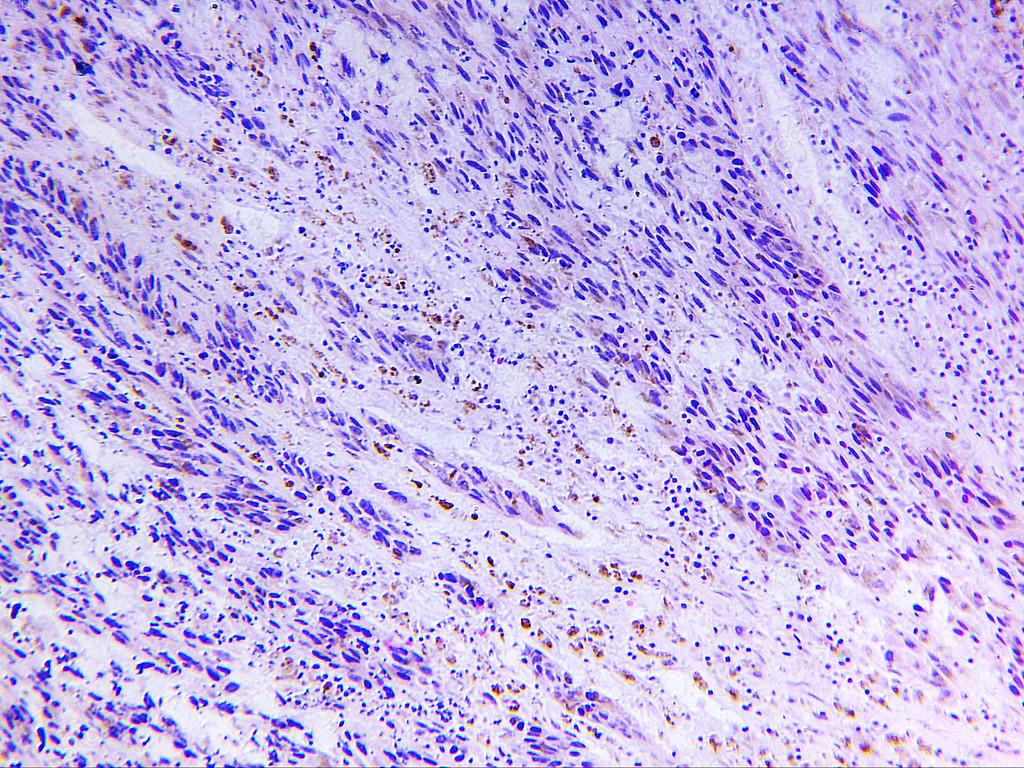

在感到奇怪之余,张小姐也觉得有些害怕,于是来到了当地三甲医院寻求治疗,医生经过专业的检查后,初步判断是“黑色素瘤”,然后让张小姐去做病理分析,不久后病理报告显示这确实是恶性黑色素瘤。

黑色素瘤的表现就和普通的痣没什么区别,它的产生是基因变异或者强紫外线照射,目前临床见得较多的是强紫外线照射后发生的黑色素瘤癌变,其他原因也有可能导致黑色素瘤。

正常人病发黑色素瘤的概率在7%左右,白种人的发病率要远高于正常人。该疾病在以前属于恶性、难治疗癌症,5年生存率仅有5%-10%,但是近些年由于医疗技术的突破,免疫疗法的兴起,黑色素瘤即使在晚期也能有较好的预后。